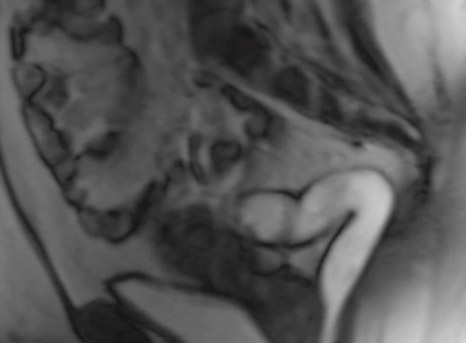

Heute analysiert der Radiologe die Darmentleerung beim liegenden Patienten mittels MRT. Dabei wird sichtbar, wie der Beckenboden im Ruhezustand, bei Muskelkontraktion und beim Pressen funktioniert. Auch sieht man, ob der Stuhlgang den "normalen" Weg nimmt oder durch sonstige Hindernisse aufgehalten wird.

Da nicht nur der Mastdarm, sondern alle Organe des Beckenbodens dargestellt werden, spricht man auch von einer dynamischen Beckenbodenuntersuchung.

Film: MRT Defäkografie